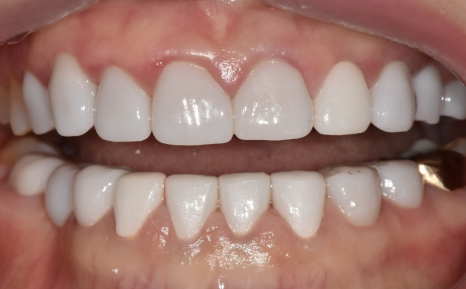

이 환자분은 누런 치아를 개선하기 위해

라미네이트를 문의하러 오셨습니다.

실제로 보니 치경부 쪽(치아와 잇몸 경계)이

전체적으로 어두웠습니다.

앞니 끝도 군데군데 깨져있었습니다.

하지만 그보다 더 큰 문제는

전체적으로 씹는 면이 많이 닳아있다는 점인데요,

이건 씹는 힘이 남들보다 강하다는 증거입니다.

그렇게 최종 완성된 치아

누런 치아 연예인치아 처럼 하얗게 만들 수 있나요?

이런 극적인 변화는 치아미백으로는 절대 불가능합니다.

반면 크라운은 색이 변하지 않아 영구적으로 하얀색을 유지하기 때문에 만족도가 높습니다.

완성 후 환자분의 얼굴 전체 인상이 환해졌습니다.